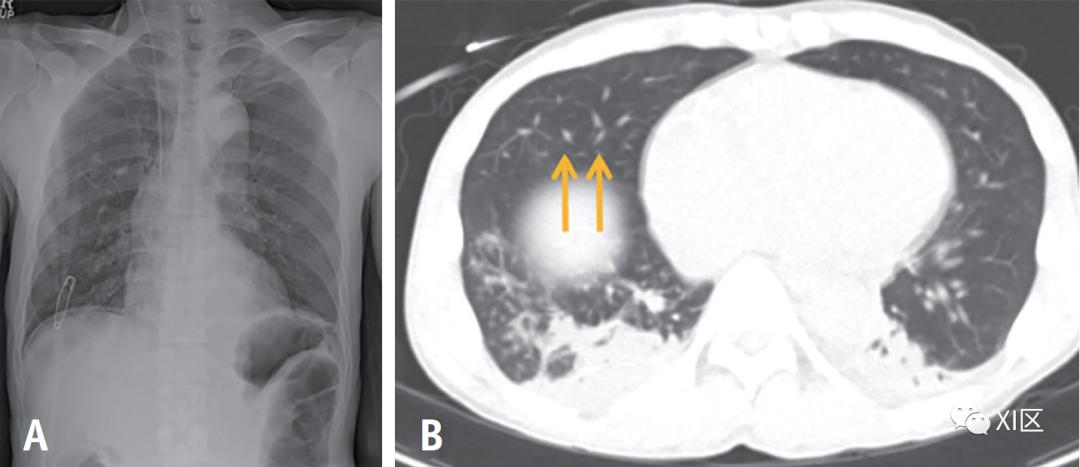

三物质分解算法能够生成肺血容量(PBV)图,该图表示碘在肺实质中的分布;它可以作为肺灌注的指标。PBV图和碘图有助于识别肺栓塞相关的灌注缺陷(图13)。此外,由于碘图显示肺结节的血供,有助于描述结节的特征(图14)。

图13 50岁男性,在远端胰腺切除术和脾切除术后第5天取出中心静脉导管后突然抱怨呼吸困难。A 术后第4天的胸部X光片显示中心静脉导管通过右颈内静脉的正常位置。B、C 术后第4天的腹部CT显示无栓塞病变的依赖性肺不张(B)。出现呼吸困难后的胸部CT图像(C)。右中肺动脉怀疑有多灶性空气(C中的箭头),这在之前的腹部CT中没有发现(B中的箭头),两个前肺都可以看到低衰减。D CT血管造影的融合图像和彩色编码碘图显示两肺前部的大灌注缺损,这可能是由肺空气栓塞引起的。